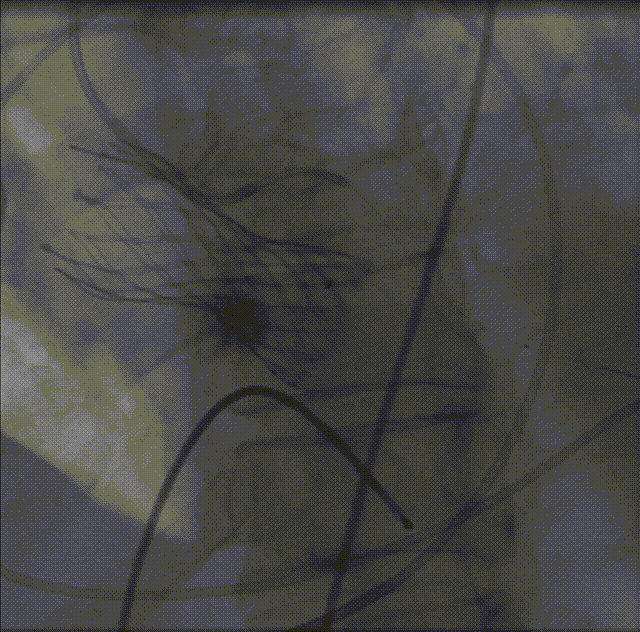

LM烟囱支架植入4.0*30mm